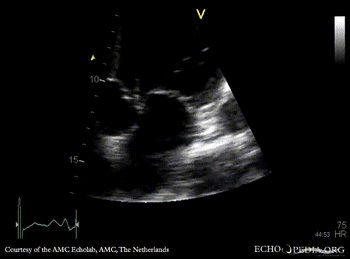

E00179.gif E00180.gif

PLAX: aortic valve vegetation, dilated left ventricle PLAX: aortic valve vegetation